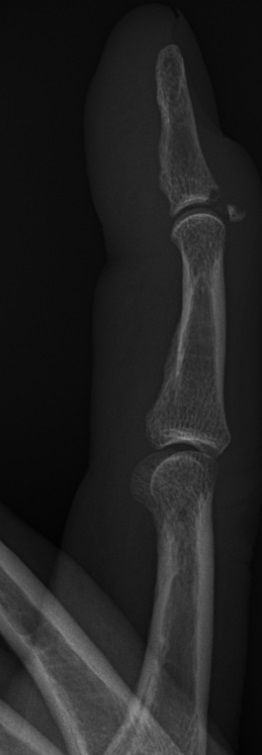

Skada: Mallet-finger/droppfinger

Oförmåga att extendera DIP-led, ev. med fraktur i distala falangen.